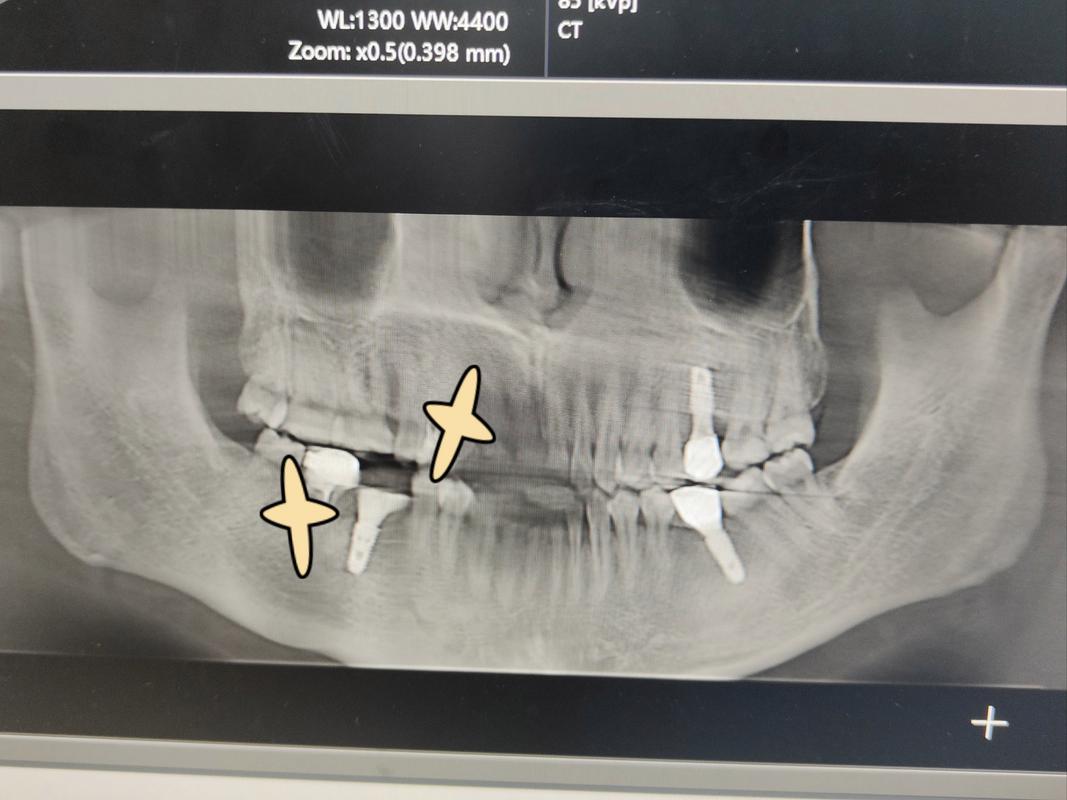

- 伪影: 钛种植体在MRI扫描中会产生少量到中等程度的伪影,伪影的大小和形状取决于种植体的尺寸、形状、位置(靠近扫描中心伪影更大)、MRI场强以及所使用的脉冲序列。

- 图像质量: 伪影会模糊种植体周围组织的图像,尤其是在种植体紧邻的区域,对于种植体本身及其与骨结合界面的评估,伪影可能会影响清晰度。

- 位置: 伪影主要出现在种植体、基台、含磁性金属牙冠及其周围区域。

- 形状: 通常表现为信号缺失的暗区(黑洞)或信号增强的亮区,形状可能不规则或呈条带状。

- 范围: 伪影范围取决于磁性物体的体积、形状、位置和MRI场强,靠近扫描中心的伪影更大。

- 可能掩盖或扭曲种植体周围的重要解剖结构(如神经、血管、肿瘤、炎症、骨结合情况)。

- 对于头颈部MRI(如脑部、颞下颌关节、鼻咽部等),如果种植牙位于扫描区域附近,伪影可能干扰对这些区域的评估。